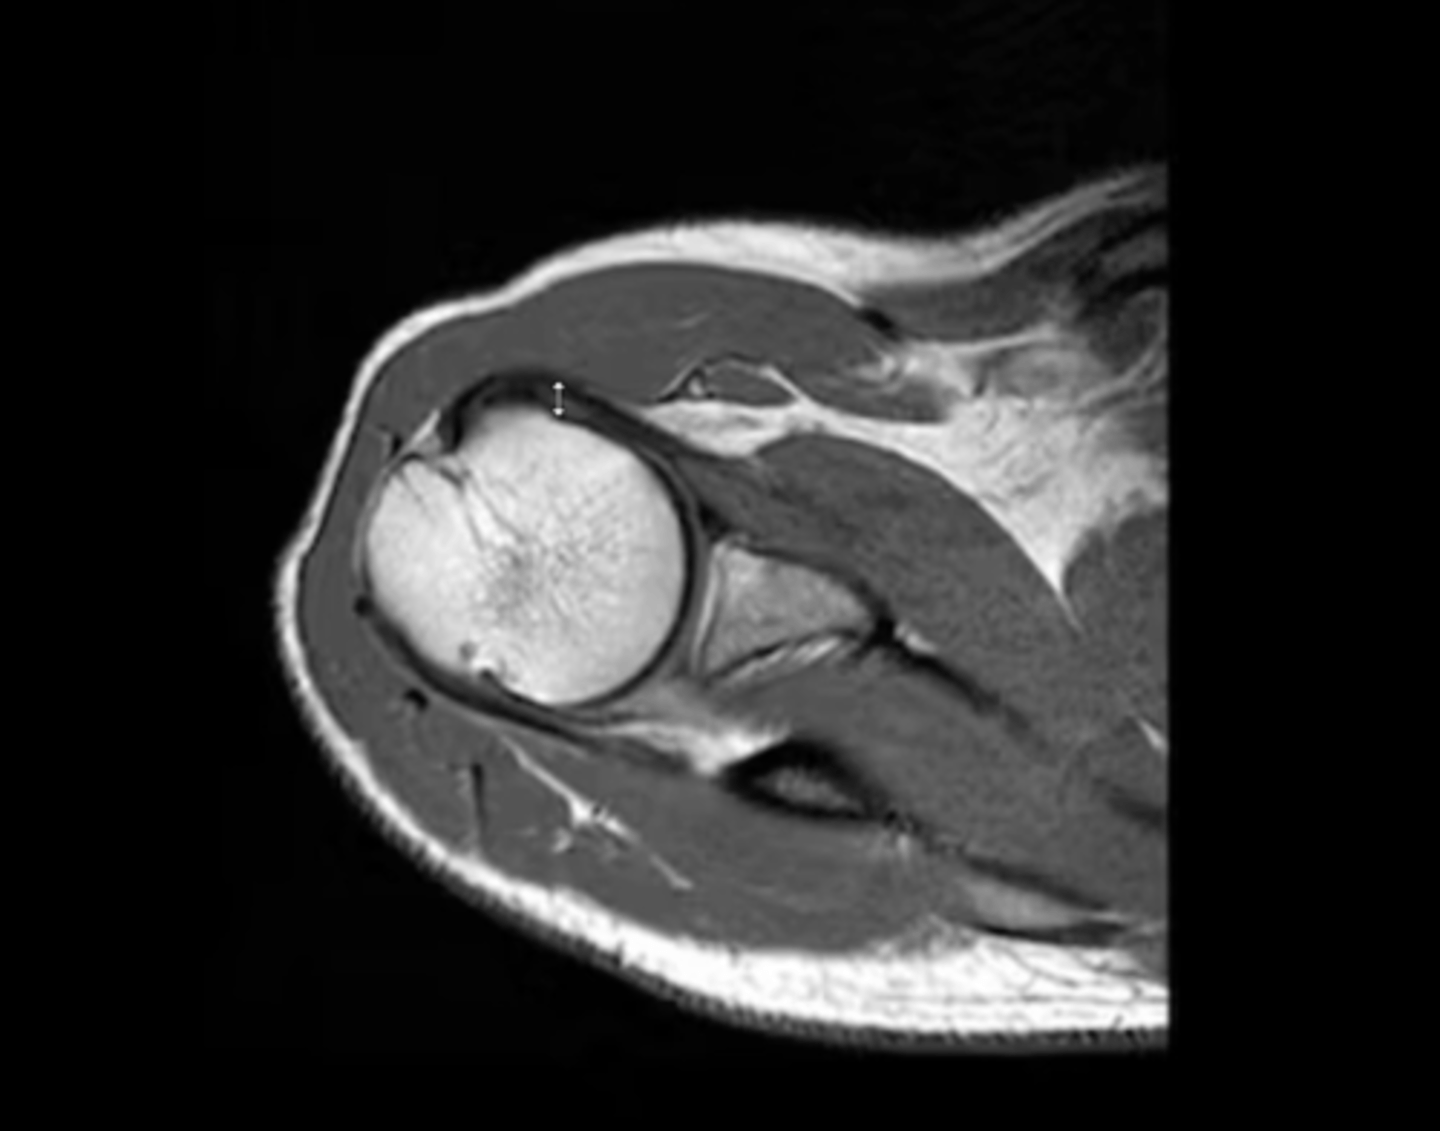

NOTE: this picture is an AXIAL view of the shoulder

An axial view of the subscapularis tendon wrapping around the anterior portion of the humerus & the infraspinatus tendon on the back side

What is this image depicting?